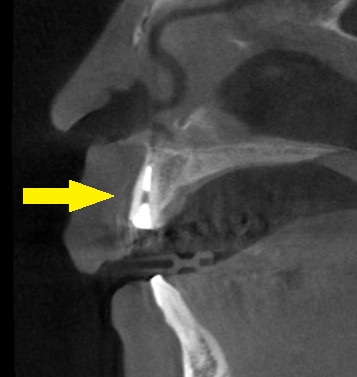

CTを撮影すると、外側、口唇側の骨がとても薄くて、抜歯して治癒を待っていると、その骨が吸収され、外側がかなり凹んでしまうと予測されました。

そこで、外側、口唇側の骨の吸収を防ぐために、歯の口唇側の一部を薄く残して、他の部分を抜歯し、そのままインプラントを埋入するという手術方法を提案させていただきました。

ソケットシールドテクニック、あるいはルートメンブレンテクニックと呼ばれる方法です。

患者様の了承が得られましたので、本日、歯根の一部をシールド状に残して抜歯し、インプラントを埋入、隙間に人工骨を填入しました。

下の写真が手術前後のCTです。